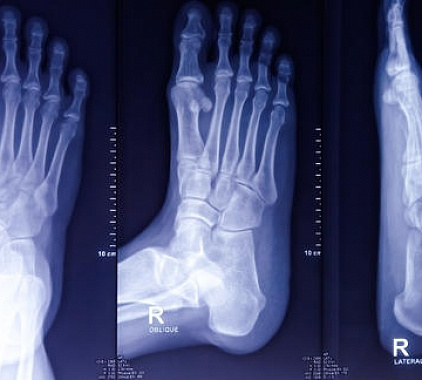

Рентген стопы – это современный и доступный метод обследования свода стоп, позволяющий определить наличие патологических изменений. Обследование основывается на проникновении рентгеновских лучей через структурные слои тканей. Процедура абсолютно безболезненна и не приносит дискомфорта. По итогу, Вы получаете снимок зоны исследования, который выдается вместе с описанием, результаты которого необходимо отдать специалисту для назначения дальнейшего лечения.

Как проходит рентген стопы

Для проведения рентгена стопы в нашем многопрофильном медицинском центре оборудован комфортный диагностический кабинет с современным рентгеновским аппаратом. В первую очередь рентгенолог поможет занять правильное положение, а также наденет на пациента средства защиты органов, не участвующих в исследовании.

В зависимости от анамнеза в направлении специалист самостоятельно выбирает проекции для сканирования:

• В прямом виде – наиболее распространена для диагностики большинства патологических состояний. Стопа устанавливается прямо на рабочий стол, что позволяет четко визуализировать голень, пятку и предплюсны;

• Боковом – используется для диагностики травматических повреждений, а также плоскостопия. Сканер устанавливается в боковой части ноги;

• Косом – в данном случае нога стоит прямо, но перемещается сам источник излучения. Данный вариант может понадобиться для более детального снимка передней части стопы.

Расшифровка результатов

Как только получен качественный снимок, врач-рентгенолог обязательно выполняет описание анатомических особенностей свода стопы в разных проекциях. Главное, что должно быть зафиксировано в заключении – это наличие переломов, новообразований, очагов воспалительного процесса и иных отклонений от нормального развития костей и тканей.

Основное, что поддается описанию на рентгене стопы, это:

• Плоскостопие. Это заключение возможно получить при выполнении обследования стопы с нагрузкой. Для этого, нога устанавливается на специальную подставку внутренней стороной по отношению к кассете рентгеновского аппарата. Результаты определяются по расчетам высоты линий от пальцев стопы до пяточной кости и градуса расположения. В норме эти значения для взрослого человека должны быть равны 35 мм и 125-130°.

• Травмы и переломы. На рентгенографическом снимке, подобные отклонения визуализируются как затемнения с неровными, нечеткими контурами. Для более детального заключения в отношении локализации, необходимо дополнительно выполнить пальцевое обследование проблемной зоны.